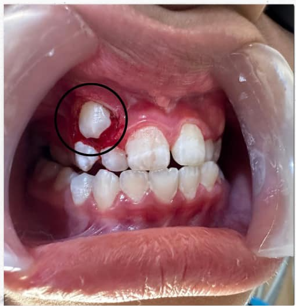

Laser Exposure – Gentle treatment to reveal impacted canine teeth.